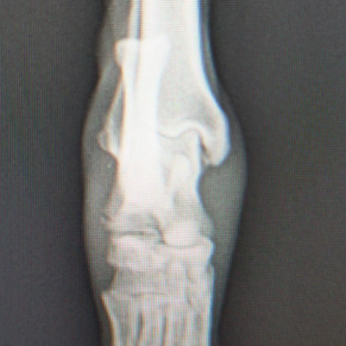

術前正面像左関節の腫れ

左足根関節の軟部組織が腫脹しています。